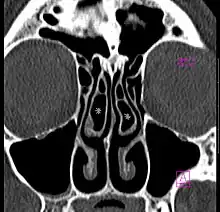

A concha bullosa is a pneumatized (air-filled) cavity within a nasal concha, also known as a turbinate.[1] Bullosa refers to the air-filled cavity within the turbinate.[1] It is a normal anatomic variant seen in up to half the population. Occasionally, a large concha bullosa may cause it to bulge sufficiently to obstruct the opening of an adjacent sinus, possibly leading to recurrent sinusitis[1] and various head pains related to areas innervated by the trigeminal nerve.[2] In such a case the turbinate can be reduced in size by endoscopic nasal surgery (turbinectomy). The presence of a concha bullosa is often associated with deviation of the nasal septum toward the opposite side of the nasal cavity.[3]